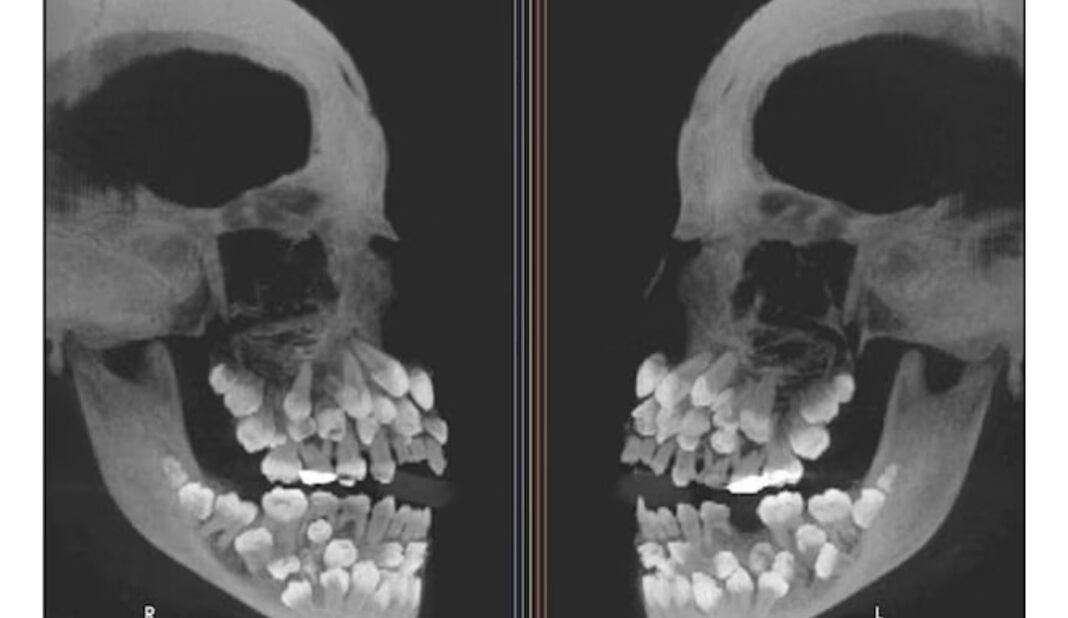

ബ്രസീലിയൻ സ്വദേശിയായ 11കാരിയിലാണ് അപൂർവങ്ങളിൽ അപൂർവമായ സംഭവം കണ്ടെത്തിയത്. സാധാരണ ഒരു മനുഷ്യന്റെ വായിൽ 32 പല്ലുകളാണ് ഉണ്ടാവുക.

സാധാരണയായി, ഹൈപ്പർഡോണ്ടിയ ബാധിതരിൽ ഒന്നോ രണ്ടോ പല്ലുകൾ മാത്രമാണ് അധികമായി വളരാറുള്ളത്. എന്നാൽ ഈ 11കാരിയുടെ വായിൽ 49 അധിക പല്ലുകളാണ് കണ്ടെത്തിയത്.

അത് കൊണ്ട് ആകെ പല്ലുകളുടെ എണ്ണം 81 ആയി. പല്ലുകൾ വായിന്റെ ഇരുവശങ്ങളിലും കൂട്ടമായി വളർന്നതായും ഗവേഷകർ പറയുന്നു.

ഈ അവസ്ഥയിൽ പല്ലുകൾ കൃത്യമായ ക്രമത്തിൽ വളരാതെ വായിനുള്ളിൽ ഒട്ടേറെ സ്ഥാനങ്ങളിൽ നിന്ന് പുതിയ പല്ലുകൾ രൂപപ്പെടും.